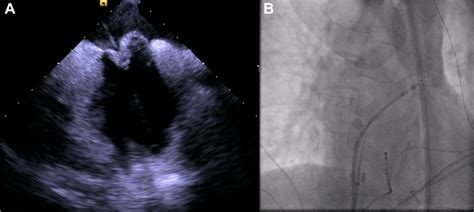

Catheter-Based Procedures These procedures involve inserting a catheter through a blood vessel to reach the heart and repair the aneurysm using small devices or implants.